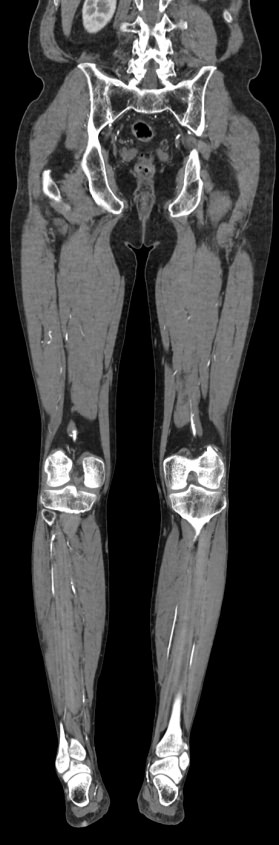

Мультиспиральная компьютерная томография является современным методом обследования сосудистой системы нижних конечностей. Такое исследование по-другому называется КТ-ангиография. Методика позволяет с помощью рентгеновского излучения получить посрезовые снимки и после цифровой обработки создать объемные модели кровеносной системы обеих ног.

В наших медицинских центрах КТ-ангиография нижних конечностей выполняется на современных мультиспиральных компьютерных томографах экспертного уровня TOSHIBA AQUILION. Аппараты послойно сканируют область исследования, одномоментно выполняя множество тончайших срезов. В результате получаются снимки высокого качества и трехмерные модели с изображением даже мелкой сосудистой сети нижних конечностей. При этом методика скоростного мультисрезового сканирования обеспечивает минимальную дозу рентгеновского облучения для пациента.

• КТ сосудов от бифуркации аорты до стопы (данный протокол обследования включает в себя полное обследование сосудов нижних конечностей, включая стопы)